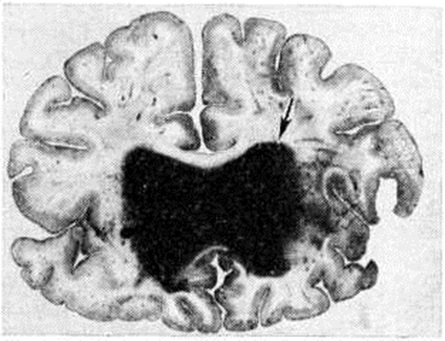

Геморрагический инсульт, как правило, возникает при заболеваниях, протекающих с повышенным артериальное давление. Это обусловлено тем, что сосудистые кризы (смотри полный свод знаний), характерные для гипертонической болезни (смотри полный свод знаний) и артериальной гипертензии (смотри полный свод знаний Гипертензия артериальная), приводят к морфологический изменениям стенок внутримозговых сосудов с нарушением их проницаемости — плазматическому пропитыванию (рисунок 1), некрозам (рисунок 2), образованию микроаневризм (рисунок 3) и их разрывам. Разрыв врождённых артериальных и артериовенозных аневризм может протекать на фоне нормального давления. Преимущественная локализация и характер геморрагий определяются особенностями ангиоархитектоники различных отделов мозга. При гипертонической болезни наиболее тяжёлым изменениям подвергаются сосуды подкорковых узлов и зрительного бугра. Это объясняется отхождением глубоких ветвей под прямым углом от средней мозговой артерии, являющейся продолжением внутренней сонной артерии, и незначительным числом анастомозов сосудов в этой области. В связи с этим на вскрытии кровоизлияния наиболее часто (40%) обнаруживаются в подкорковых узлах с распространением в прилежащее белое вещество (так называемый латеральные кровоизлияния, то есть расположенные латерально от внутренней капсулы, рисунок 4). Второе место по частоте (16%) занимают обширные кровоизлияния, разрушающие подкорковые узлы, внутреннюю капсулу, зрительный бугор (так называемый смешанные кровоизлияния — рисунок 5). Кровоизлияния в зрительный бугор (так называемый медиальные — рисунок 6) составляют 10%, в мозжечок — 6—10%, в мост мозга — 5% от общего числа внутримозговых геморрагий. Кровоизлияния только в белое вещество полушарий мозга встречаются крайне редко. Подразделение полушарных кровоизлияний на латеральные, медиальные и смешанные имеет особое значение в связи с хирургическим лечением геморрагического Инсульт.

Кровоизлияния типа геморрагического пропитывания возникают преимущественно в зрительных буграх, реже в мосту мозга и составляют 15% внутримозговых кровоизлияний. Они являются результатом слияния мелких очагов кровоизлияний, возникающих путём диапедеза из мелких сосудов, имеют вид очагов красного цвета, дряблой консистенции и в силу внешнего сходства иногда напоминают геморрагический инфаркт. В первые часы Инсульт нарушается проницаемость сосудов на границе с кровоизлиянием, развивается отёк; кровь распространяется по ходу нервных волокон. К концу первых суток наблюдаются лейкостазы и лейкодиапедез, размеры очага увеличиваются за счёт диапедезных геморрагий и некробиотических изменений в отёчном веществе мозга. Через двое суток начинается процесс репарации — появление зернистых шаров и гипертрофированных астроцитов; позже образуется вал из астроглии и новообразованных сосудов, кровь подвергается гемолизу, появляются макрофаги с гемосидерином, образуются аргирофильные и коллагеновые волокна. Исходом кровоизлияния может быть формирование глиомезодермального рубца или кисты, содержащих гемосидерин (рисунок 9). В 80—85% кровоизлияний на вскрытии выявляется прорыв крови в желудочки, значительно реже — в подпаутинное пространство. В последнее кровь может также проникнуть из четвёртого желудочка. Первичные вентрикулярные геморрагии нетравматического генеза — явление казуистическое. При разрыве врождённых аневризм артерий основания мозга возникают первичные субарахноидальные кровоизлияния, которые обычно локализуются на базальной поверхности или в латеральной борозде; иногда кровь проникает в субдуральное пространство; часто повреждается вещество мозга (субарахноидально-паренхиматозные кровоизлияния). Расположение гематом, образующихся при этом, зависит от локализации аневризмы, обычно это базальный отдел лобной доли или височная область. В части случаев при незначительном субарахноидально-паренхиматозном кровоизлиянии возможен массивный прорыв крови в желудочки (рисунок 10), что иногда ошибочно диагностируется как первичное вентрикулярное кровоизлияние.